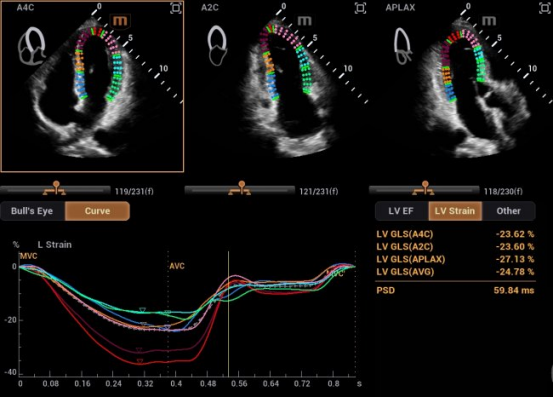

在研发中,迈瑞研发团队另辟蹊径,推出了自动左心室应变评估 Auto Strain LV 。该功能不再依赖心电信号作为“时间坐标”,而是让AI直接识别心脏机械运动的关键节点——当二尖瓣关闭、主动脉瓣开放,这些瓣膜运动的瞬间,就是心脏收缩与舒张的自然锚点。

迈瑞也在与尹立雪教授团队牵头的合作项目中,挖掘出自动左心室应变评估 Auto Strain LV 更多的临床应用价值,成功让心肌应变检测技术摆脱“心电图(ECG)”的束缚。尹教授表示:“基于人工智能的图像技术,现在已实现无需同步心电图的自动心肌应变分析。该技术操作便捷,检测结果与传统方法高度一致,且能早于传统指标识别心肌功能异常,为疾病早期干预提供关键支撑。”